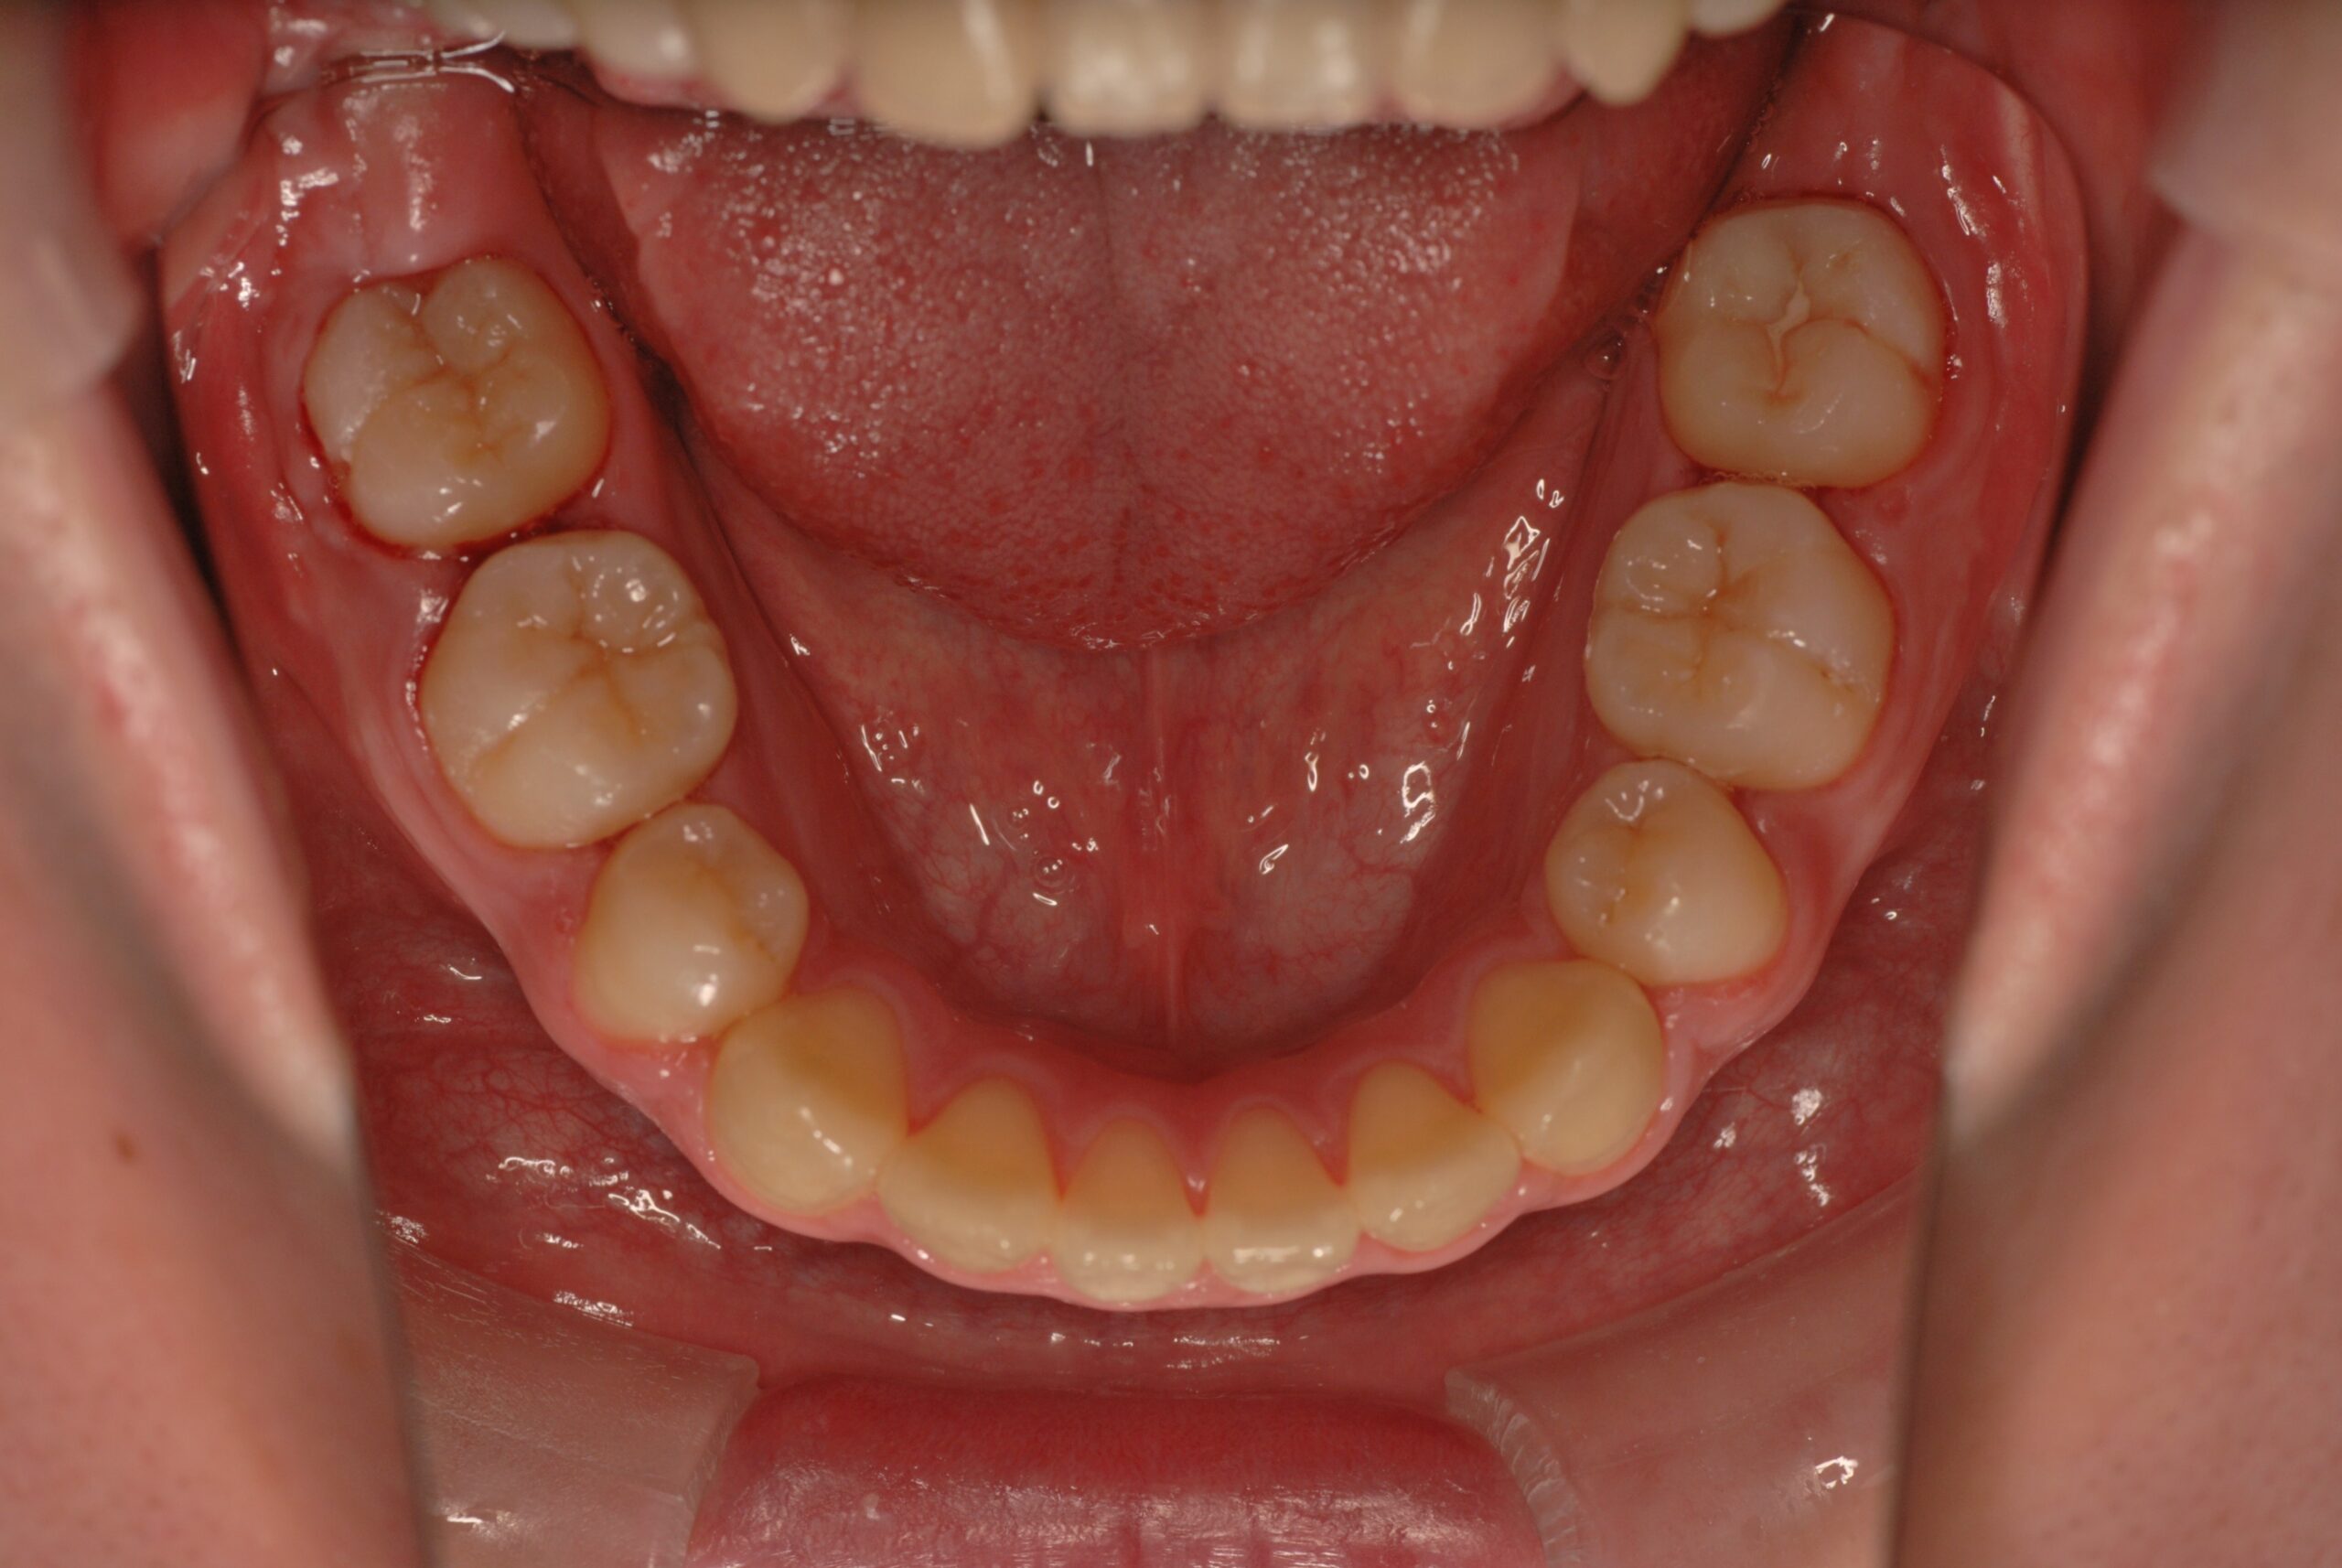

反対咬合(受け口、下顎前突) 叢生

- 骨格性下顎前突症、下顎骨左偏位、叢生、 顎変形症として、外科的矯正術を計画。 叢生、右側第2大臼歯鋏状咬合。 上下顎第一小臼歯を抜歯し、抜歯空隙を利用し叢生を改善し、上下顎それぞれ歯列を整列し、矯正治療中に病院歯科口腔外科にて外科手術(近郊の病院歯科口腔外科にて、口の中から手術、2週間入院)により下顎骨の後退と左偏位の改善をし、適切なオーバージェット、オーバーバイトを付与する。